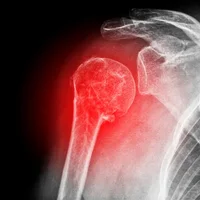

Diagnostic : le diagnostic de la luxation du genou est généralement confirmé par une radiographie ou une IRM.